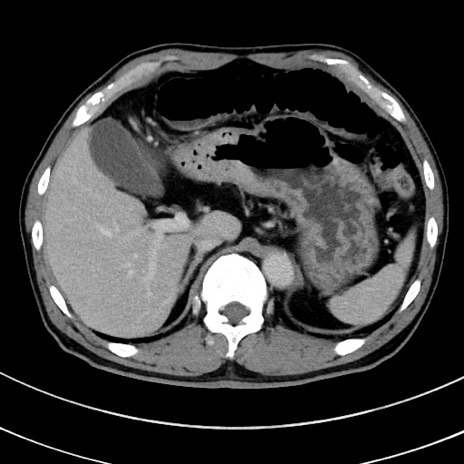

症例8(横断像)

【症例】 60歳代男性

【主訴】 黒色吐物

【現病歴】 4日前から嘔気自覚、2日前の朝食後にも嘔気あり、自分で手で嘔吐反射起こし嘔吐したところ血が混ざっていたため受診。

【既往歴】 5年前汎発性腹膜炎を伴う急性虫垂炎で手術、高血圧、前立腺肥大症、高脂血症

【身体所見】 腹部正中に手術癩痕あり 腹部平坦・軟圧痛なし膨満感あり

【データ】WBC 8400、CRP 4.54